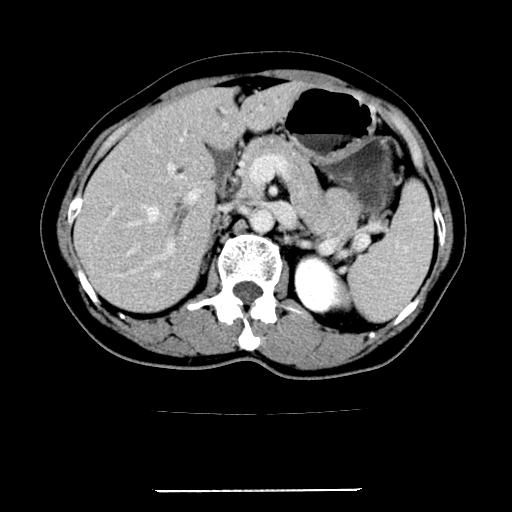

标题: CT22301:女,67岁,上腹部疼痛一周伴皮肤黄染,无发热。 [打印本页]

女,67岁,上腹部疼痛一周伴皮肤黄染,无发热。

左叶肝内胆管结石,并远端肝内胆管扩张。

考虑:肝内胆管结石继发肝内胆管扩张,右肾旋转不良。

肝内外胆管结石并肝内胆管扩张。

建议薄层观察,除外肝门部胆管细胞癌

考虑肝胆管癌;胰头占位?【形态失常,体积增大】

1、肝门高密度影下层面和胰头层面可见轻度胆管扩张,而静脉和延迟期均未见扫描完胰头,不能完全排除胰头占位。2、肝门部高密度影,考虑钙化或结石。

考虑肝门胆管癌伴门脉左支受侵包埋,建议mrcp进一步检查。